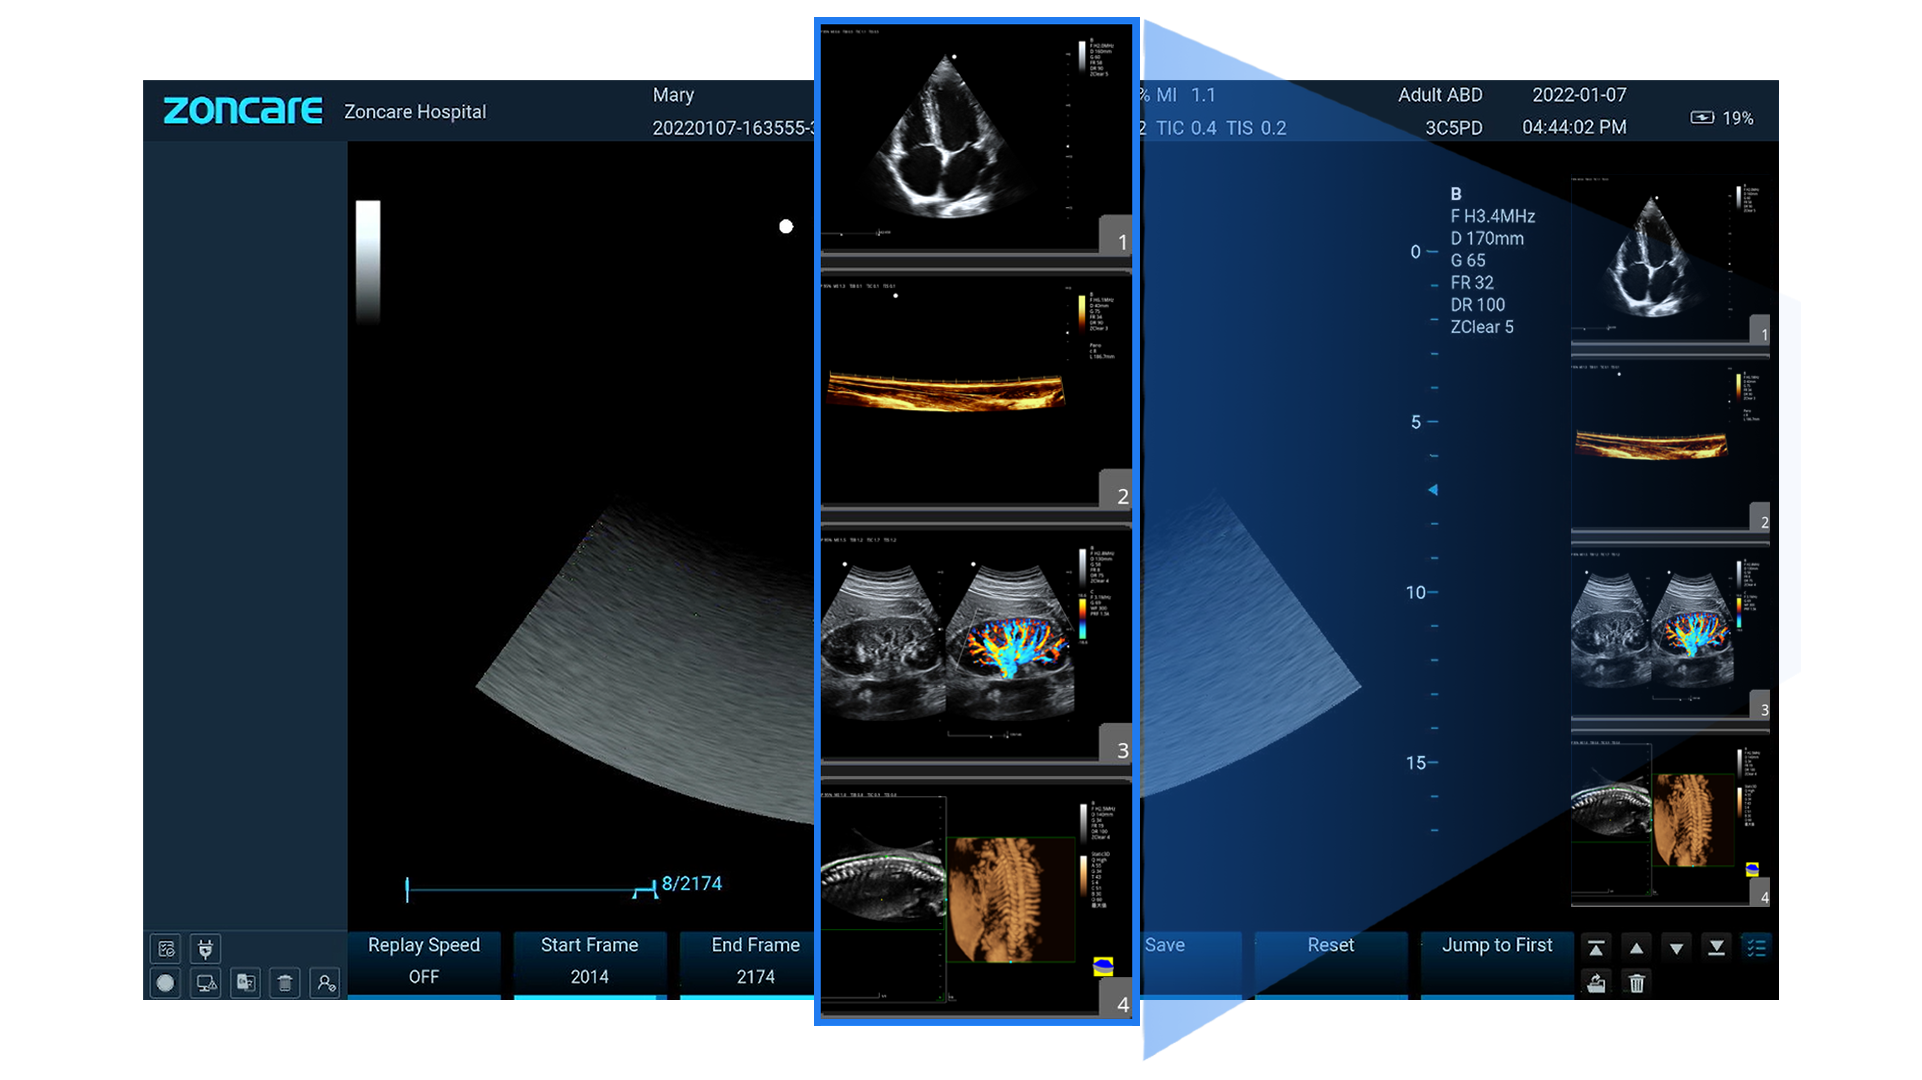

Modos de Imagen

-

B, B-Steer, M, B/M, 2B/4B

-

Color Doppler (CDFI), Power Doppler (PDI/DPDI)

-

Doppler Pulsado (PW) y Continuo (CW)

-

Anatomic M (recto y curvo)

-

TDI (TVI, TVD, TVM, TEI)

-

Panorámico y Color Panorámico (EFOV)

-

Elastografía

-

3D / 4D (ZLive, Silhouette)

Almacenamiento, Datos y Conectividad

-

Disco interno: 1 TB

-

Formatos: RAW, DICOM, JPG, BMP, TIFF, AVI, MP4